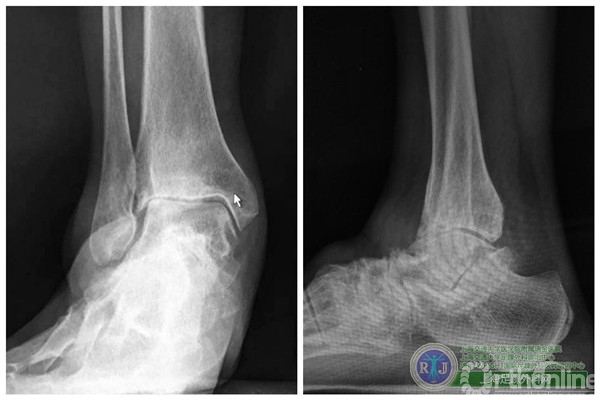

患者,顾XX,女,57岁,因“右踝类风湿性关节炎关节肿痛、活动受限15年,加重1年”入院。上海瑞金医院足踝外科接诊检查后发现该患者右踝关节软骨破坏严重,关节活动严重受限,经与患者反复沟通、解释病情,最终患者要求进行全踝关节置换手术。

上海瑞金医院骨科足踝外科团队于2015年10月28日上午成功对该患者实施了第三代全踝关节假体(INBONE® II. Wright.)置换手术,手术过程非常顺利。手术中首先清理踝关节内外侧炎性组织及骨赘,将患足置于专门的定制支架中,在透视下反复调整足踝及导针位置,力求最高精确度。在截骨导板的定位下进行踝关节胫骨及距骨的截骨,试样假体大小,置入合适匹配的踝关节假体及垫片完成全踝关节假体的置换,全程手术时间90分钟。完成的全踝关节假体置换位置精确,假体设计稳定牢固,踝关节内外侧软组织平衡,达到了预期的效果。术后患者恢复良好,手术取得圆满成功。患者在休养五周左右以后可以下地行走,去除踝关节炎疼痛畸形的同时能够保留踝关节的活动度,为生活和工作提供极大便利。